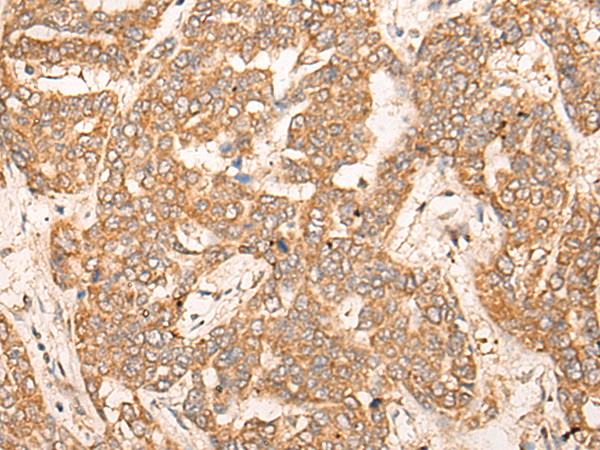

ELISA, IHC |

IHC positive control: |

Human liver cancer |

IHC Recommend dilution: |

25-100 |